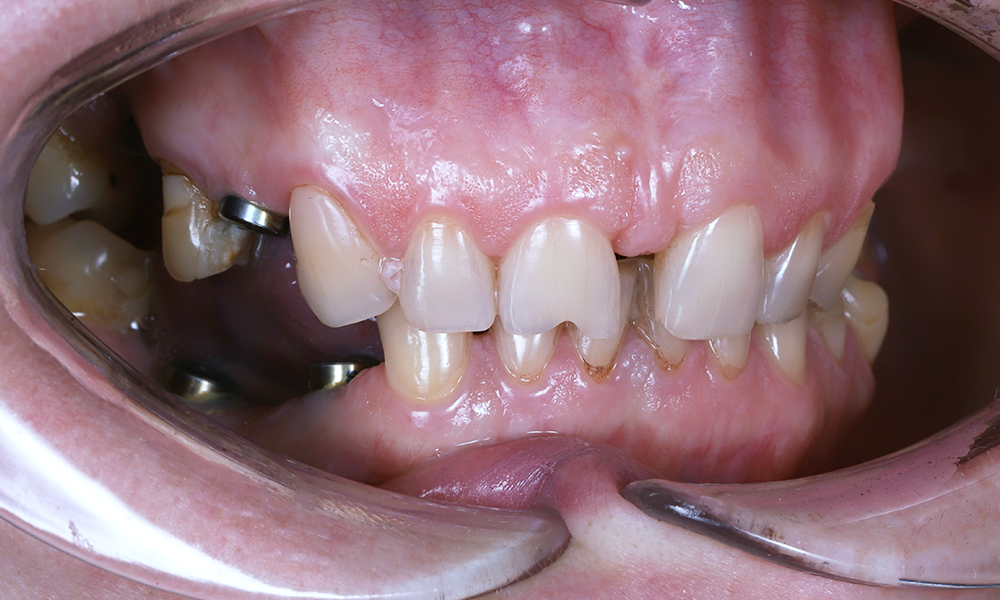

До

Какая ситуация была изначально?

- У пациентки отсутствовали боковые зубы.

- Была выраженная диастема — заметный промежуток между передними резцами.

- Стираемость зубов.